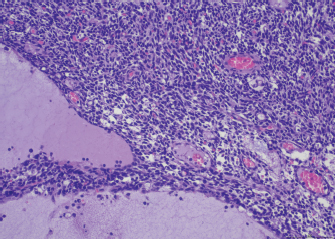

Fig. 2. Heart, dog. Myocardial interstitium is infiltrated by lymphocytes, with myofiber degeneration and necrosis. Hematoxylin and eosin.

A necropsy was performed. The main macroscopic finding consisted of a diffused megaesophagus. Low numbers of white, small-sized spots were also visible on the myocardial surface, with random distribution. The subsequent histology of the heart showed that myocardium was infiltrated by a severe multifocal to coalescing inflammatory process, mainly composed of lymphocytes, admixed with a lower number of macrophages, plasma cells and neutrophils, and rare giant multinucleated cells, with up to five haphazardly arranged nuclei. Inflammatory infiltrate was associated with small foci of necrotic cardiomyocytes with hypereosinophilic cytoplasm, loss of cross striations and pyknotic nuclei (Fig. 2). A similar inflammatory process consisting of multiple, variably sized foci of necrotizing myositis also involved esophageal and diaphragmatic skeletal muscle. Immunohistochemistry (IHC) was performed to characterize the inflammation involving the myocardium, esophagus and diaphragmatic skeletal muscle: the inflammatory cell population infiltrating the myocardium was mainly composed of CD3+ lymphocytes (T cells), admixed with a lower number of Iba1 positive macrophages, most of them being MHC-II positive. Rare, scattered B lymphocytes expressed CD20. Interestingly, a low proportion of cardiomyocytes expressed MHC-II in the cytoplasm or on the sarcolemma. Esophageal and diaphragmatic skeletal muscles were also characterized by an infiltration of T lymphocytes and macrophages. The histopathological picture was consistent with lymphocytic and necrotizing myocarditis and polymyositis.

In veterinary medicine, Shelton et al. (2001) documented antistriational antibodies against titin and RyR in dogs with MG thymoma associated and found an association between the presence of RyR antibodies and more severe disease. An association between MG thymoma associated and polymyositis has also been described in the dog (Darke et al., 1975; Aronshon et al., 1984), while there are no reports of MG with associated GCM or myocarditis. Third-degree atrial ventricular heart block has been described in some dogs with MG thymoma associated, but in these cases, an idiopathic cardiac conduction disturbance was hypothesized (Hackett et al., 1995). In the present report, myocarditis was suspected as a pathological mechanism of the patient's severe arrhythmia, and the marked increase in serum troponins supported this diagnostic hypothesis. Post-mortem myocardial histological examination confirmed the association between third-degree heart block and myocarditis. According to cells morphology, the myocarditis exhibited by the dog is similar to the human GCM type, and the detected histopathological picture could represent a GCM variant in dogs: both entities are characterized by infiltration of CD3 lymphocytes, associated with myofiber damage. Compared to GCM, case a lower number of giant multinucleated cells was detected in the present. Supporting the presence of an immune-mediated mechanism was also the expression of MHC II on the sarcolemma of myocardial cells. The muscle tissue does not usually express MHC II in healthy conditions, and its expression is typical of immune-mediated diseases, even though it is not exclusive (Paciello et al., 2007; Durward-Akhurst and Valberg, 2018). This histological type of inflammatory myopathy, already reported in skeletal muscles of dogs with polymyositis and MG associated thymoma (Darke et al., 1975; Shelton et al., 2001), is similar to that described in polymyositis of human patients with thymoma and MG (Kon et al., 2013). The severe increase in our patient's muscle enzymes, in association with the patient's poor response to traditional MG therapy, could also clinically suggest concomitant polymyositis. Unfortunately, no electrodiagnostic test was performed to confirm the clinical suspicion of polymyositis. However, histopathological findings of esophageal and diaphragmatic muscles and increased muscle enzymes support the presence of an inflammatory process. After the exclusion of the main infectious causes, an immunomediated syndrome is strongly suggested. Although the presence of antistriational antibodies was not investigated in our case, the severity of the clinical signs exhibited by the dog was comparable with the clinical signs generally showed by MG human patients with polymyositis in the presence of antistriational antibodies. To our knowledge, this is the first report of thymoma-associated MG with concurrent myocarditis and polymyositis in a dog. Further studies will demonstrate the correlation between myocarditis and antistriational antibodies in veterinary patients with thymoma associated MG.